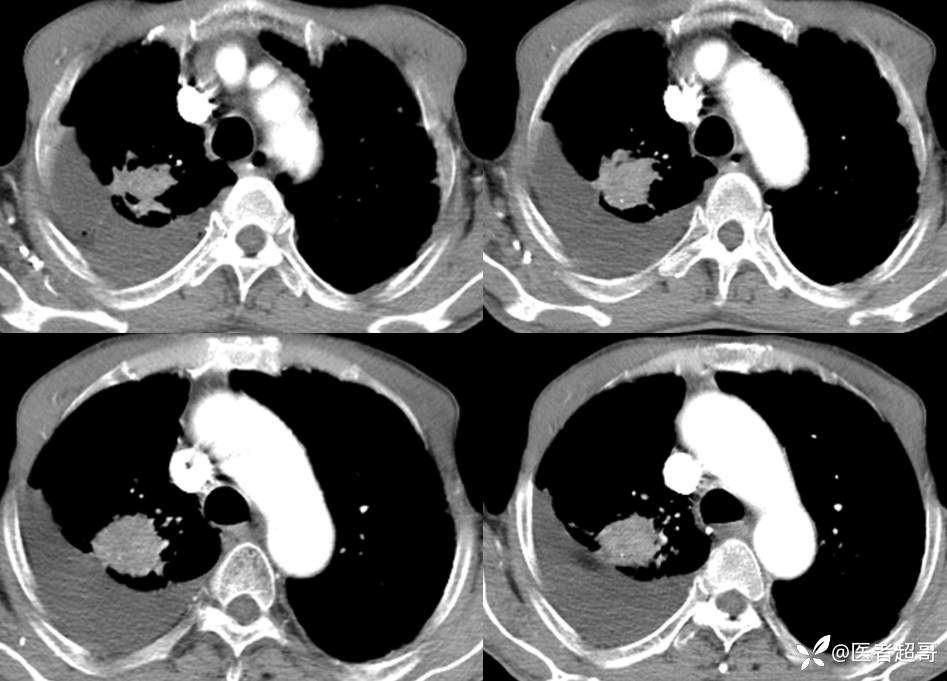

患者,男,72岁,农民,于2021年05月26日17时20分因"发作性精神行为异常10+天"入院。@丁香影像频道